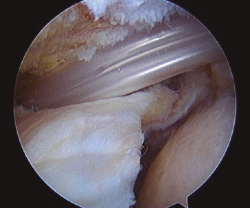

El ascenso de la cabeza humeral durante la contracción del deltoides es el origen biomecánico de la disfunción del hombro y de la degeneración articular cuando se produce una rotura masiva del manguito. Para combatir este fenómeno se desarrolló la técnica del espaciador subacromial biodegradable, cuyo objetivo es mantener la cabeza centrada durante la contracción del deltoides(12)(Figura 1). Sin embargo, la experiencia derivada de su uso es todavía limitada, sin que se hayan definido con exactitud los resultados ni las complicaciones a medio o largo plazo.

Figura 1. Implantación del espaciador subacromial previa a su relleno con suero salino.